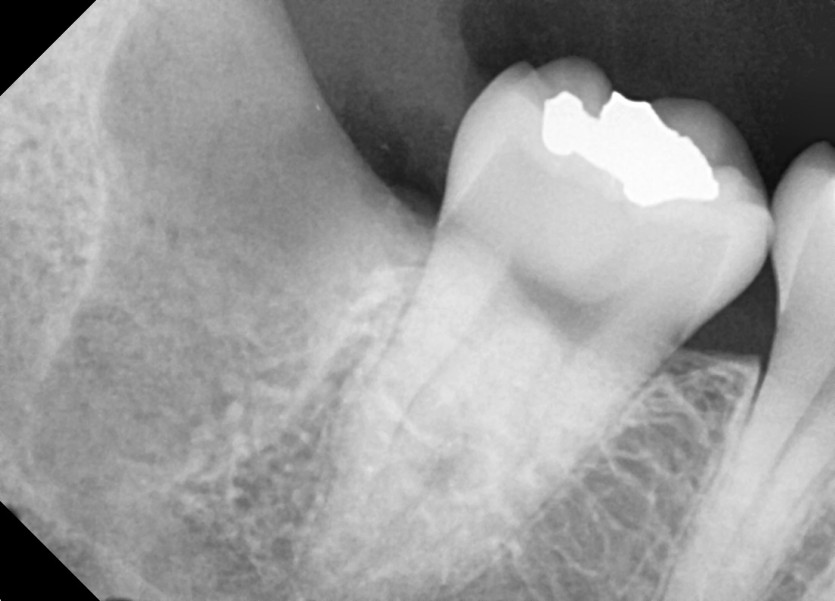

#48 사랑니 발치

구강외과 전문의가 당일 발치했습니다.